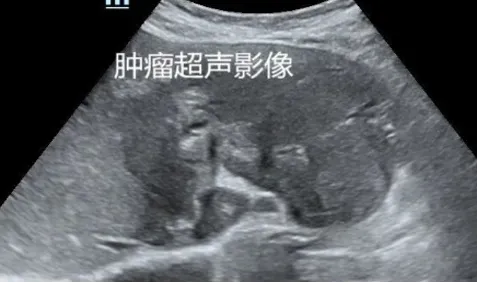

转移性肝癌

定义

● 是肝内最常见的继发性肝恶性肿瘤。

● 来源:转移性肝癌多来自于腹腔内肿瘤约占2/3,包括食管、胃肠道、胆囊、胰腺等消化系统恶性肿瘤居多。

● 不合并肝硬化。

病理特点:

瘤体快速增长,边缘瘤组织往往保持活跃的细胞生长结节内部,尤其瘤体中央区或中心发生不同程度缺血造成慢性组织变性、点片状坏死等不均质改变,伴随反复组织修复和结缔组织增生,有的发生液化坏死。

超声表现

● 圆形或椭圆形。

● 常多发,也可单发,在较大的转移性肝癌中可出现多结节相互融合,形似“葡萄串征。

● 内部回声多样,周边低回声的声晕(较宽)。

● 极少合并肝硬化。

● 少血供。

超声特点

● 牛眼征:有较宽的低回声晕,形似牛眼多见于腺癌肝转移。

● 高回声:多见于消化道恶性肿瘤。

● 低回声:常见于乳腺癌等。

● 囊性变型:多见于胃肠间质肉瘤、卵巢囊腺癌等。